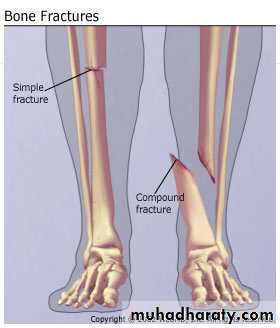

According to presence of a wound

- closed fractures

- open fractures